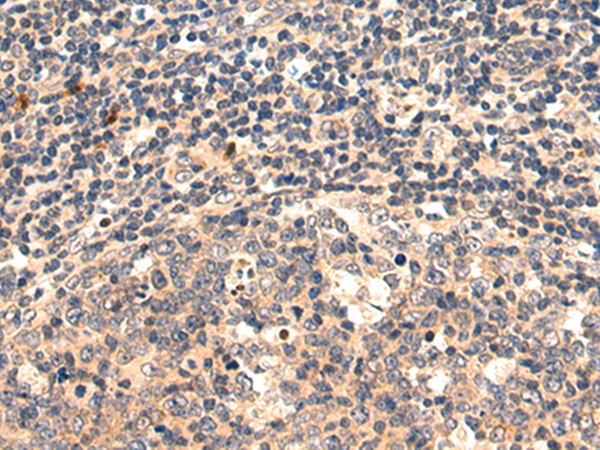

分类: 科研抗体货号: P06279别名:应用: WB,IHC反应种属: Human, Mouse, Rat

分类: 科研抗体货号: P06217别名: NEM7应用: WB,IHC反应种属: Human, Mouse, Rat

分类: 科研抗体货号: P06266别名: NCBP; Sto1; CBP80应用: WB,IHC反应种属: Human, Mouse, Rat

分类: 科研抗体货号: P06210别名:应用: WB,IHC反应种属: Human, Mouse, Rat

分类: 科研抗体货号: P06263别名: CML3; NACED; NAT8-LIKE应用: WB,IHC反应种属: Human, Mouse, Rat

分类: 科研抗体货号: P06205别名: CACC; GOB5; CACC1; CLCRG1; CaCC-1; hCLCA1; hCaCC-1应用: IHC反应种属: Human

分类: 科研抗体货号: P06262别名: DNAS1L2应用: IHC反应种属: Human, Mouse

分类: 科研抗体货号: P06202别名: AMY; CLAC; CLACP; CFEOM5; CLAC-P应用: WB,IHC反应种属: Human, Mouse

分类: 科研抗体货号: P06261别名: DCR2; CD264; TRUNDD; TRAILR4; TRAIL-R4应用: WB,IHC反应种属: Human